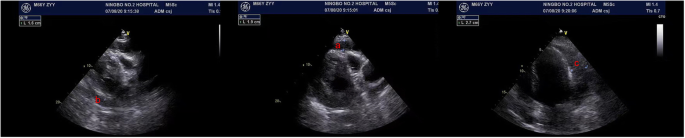

A 66-year-old male was admitted to Ningbo Hwa Mei Hospital in July 21, 2020 because of repeated pericardial effusion. He underwent PCI due to Coronary Atherosclerotic Heart Disease in July 3, 2020. He complained pectoralgia for 1 week before hospitalization. Echocardiography showed massive pericardial effusion. Percutaneous pericardiocentesis was performed and about 2400 ml hemorrhagic effusion was drained in the next 6 days. Chest Computed Tomography(CT) and echocardiography on August 7th showed massive pericardial hemorrhage with blood clot. Operation was advised. But the patient claimed explicitly that he would rather die than have a sternotomy because of his concern about the incision infection due to the diabetes and obesity and the disunion of the sternum due to the osteoporosis which caused by renal failure he had suffered for several years. So we performed a minimally invasive surgery.

The pericardium was caught by double joint oval forceps and lift up. After the blood clot under the incision was excavated by another double joint oval forceps, the thoracoscope was inserted into the pericardial cavity through the pericardial incision. Take the advantage of the 30°slope of the thoracoscope, we can observe different directions by turn the scope without move the shaft. To obtain a better view, we used a curved double joint forceps to enlarge the pericardial cavity by using the turning of the forceps to lift the pericardium. After cleaning the left part of the pericardial cavity, we turn the scope to the anterior and right lateral cavity to clean the blood clot until the level of superior vena cava. It is hard to avoid squeezing the heart during the procedure, so the ECG(Electrocardiogram) and blood pressure must be payed attention to during the operation. A drainage tube was insert into the pericardial cavity and the incision was sutured in layers. Another drainage tube was placed in the pleural space under direct vision and connected to underwater seal. The postoperative course was uneventfull. He was discharged 7 days after the operation. A chest CT on October 11th showed there was almost no pericardial effusion left (Fig. 1, Fig. 2).